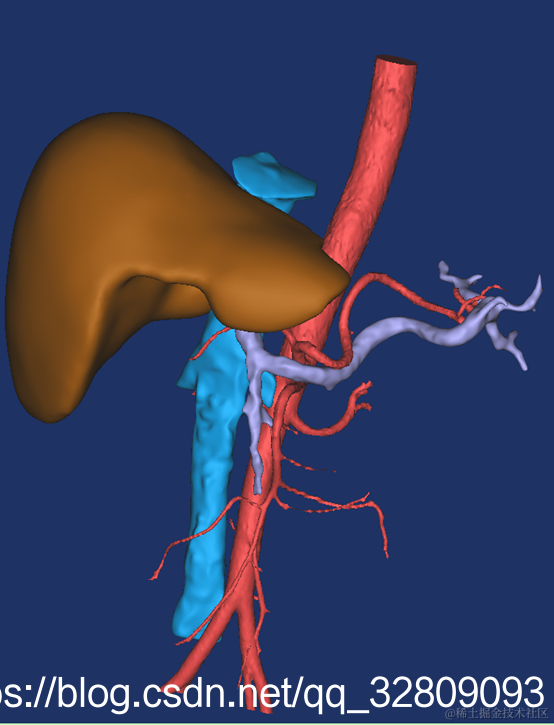

最后建模出来的效果:

正面图(肝脏+动脉+门静脉+腔静脉)                                反面图                                                          透视图

三种视图: